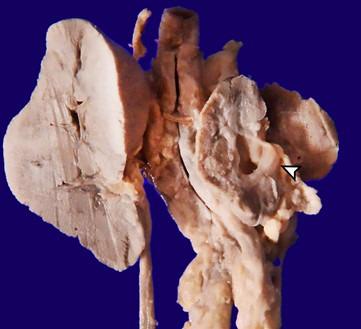

We present a case of a late preterm intrauterine growth-restricted neonate with isolated and persistent severe thrombocytopenia. At birth, the neonate did not have a complete clinical spectrum of congenital rubella syndrome (CRS) but later developed peculiar findings that helped clinch the diagnosis. The neonate also had interstitial pneumonia and died secondary to superimposed acute viral infection leading to acute respiratory distress syndrome. The serology was positive for IgM antibodies against the rubella virus. The constellation of clinical manifestations of congenital rubella in the presence of positive IgM antibody against rubella and consistent histopathology confirmed the diagnosis of CRS.

我们报告一例晚期早产儿,其宫内生长受限,伴有孤立且持续的严重血小板减少症。出生时,该新生儿并无先天性风疹综合征(CRS)的完整临床症状,但后来出现了有助于确诊的特殊表现。该新生儿还患有间质性肺炎,继发于叠加的急性病毒感染,导致急性呼吸窘迫综合征。血清学检测显示风疹病毒IgM抗体呈阳性。在风疹IgM抗体阳性且组织病理学一致的情况下,先天性风疹的一系列临床表现确诊了CRS。